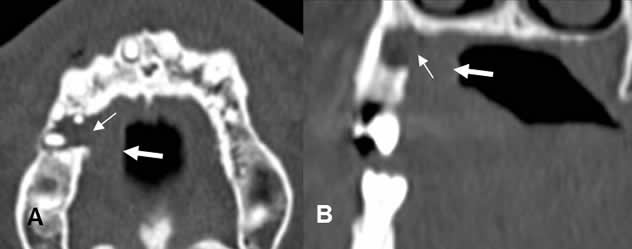

Fig 48. Absceso periapical.

A: TAC reconstrucción y B: TAC reconstrucción coronal. Enfermedad periapical, con destrucción ósea (Flechas delgadas) y prominencia de los tejidos blandos, hacia la superficie lingual (Flechas gruesas), por la formación de absceso periapical.